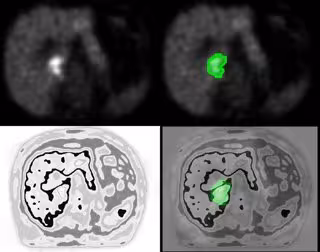

Una nueva técnica, basada en la utilización de un algoritmo, permite obtener una precisión mucho mayor en la delimitación de los tumores de hígado, según un estudio de la Universidad de Alcalá de Henares (Madrid).

Este nuevo sistema, que ha sido presentado en el Congreso de la Sociedad Europea de Radiología y Oncología (ESTRO), permite mejorar la delimitación hasta en un 45 por ciento y facilita la radiación del tumor sin destruir tejido sano. Todo ello reduce el tiempo de recuperación del paciente y las complicaciones en el postoperatorio.

La investigadora del grupo RSG, Rocío Sánchez, ha afirmado que "este algoritmo mejora la calidad de la imagen, haciéndola más precisa y concretando lo que es y lo que no es lesión tumoral". Hasta ahora no existían instrumentos para delimitar el volumen de los tumores de hígado y lo que se hacía era sobredimensionar la lesión, lo que puede ser "problemático" cuando los tumores se encuentran en órganos vitales o próximos a ellos.